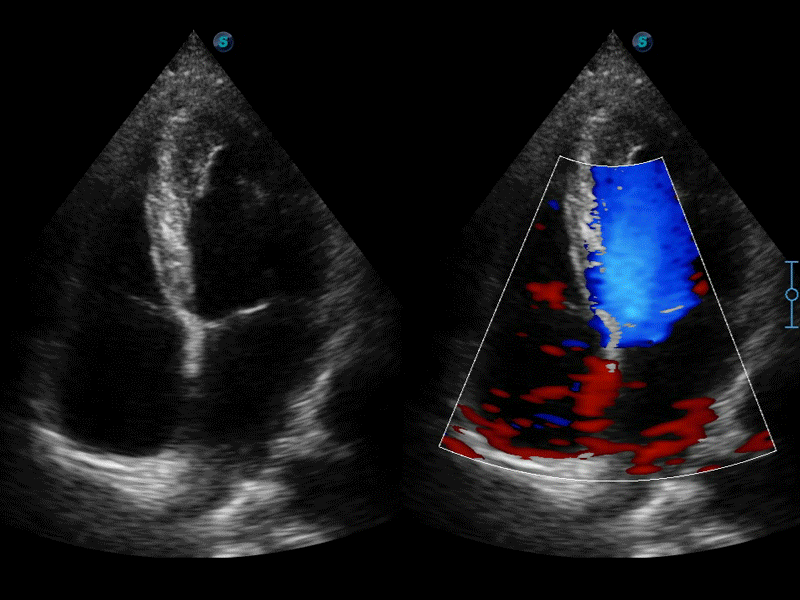

高分辨率血流成像技术提高了对低速血流信号的检测能力。在提高空间分辨率的同时,也克服了血流外溢现象,为用户提供更加真实的血流动力学信息。

自动识别收缩和舒张末期心肌内膜,自动计算射血分数EF值。